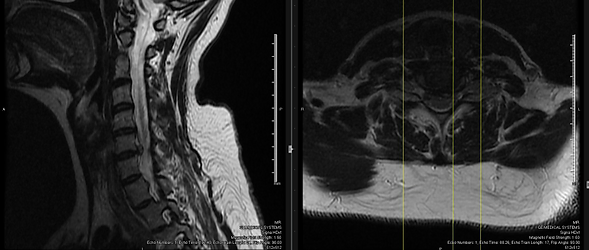

- MRI of the cervical spine was ordered

- On 10/21/2016 (7 months after first visit) patient reported new increased pain in the cervical spine.

- Pain was reported as severe, shooting, sharp and stabbing rated 9/10

- Patient further reported new pain shooting down to the left shoulder and left arm